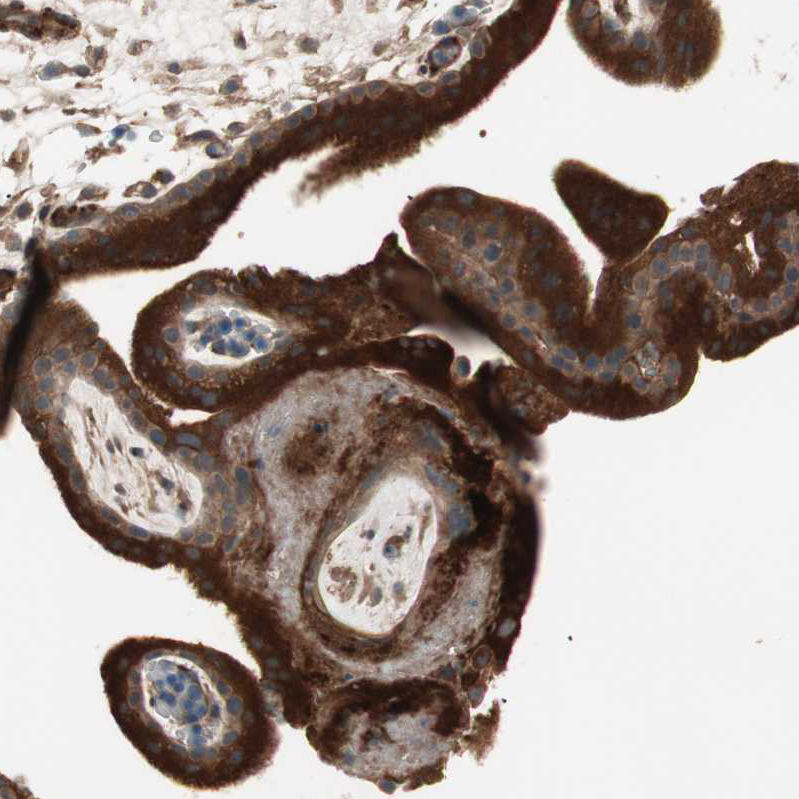

Immunohistochemical staining of human placenta shows strong cytoplasmic positivity in trophoblastic cells.